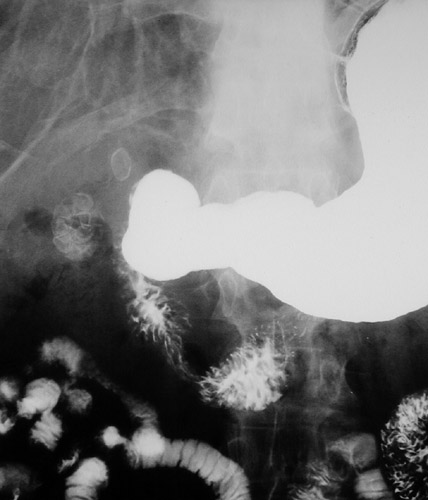

This upper GI series radiograph reveals the presence of

multiple gallstones

within the gallbladder as well as another

stone impacted in the cystic duct

.